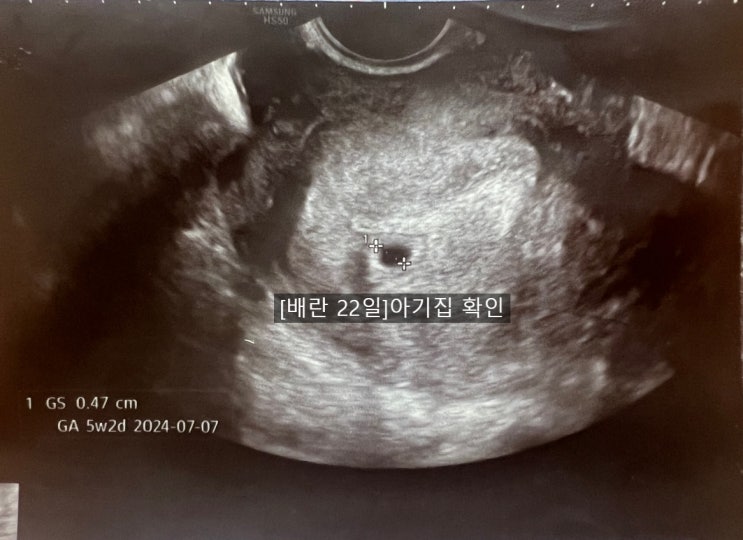

배란 22일(임테기역전/아기집확인/병원초음파차이)

배란 22일 어제 임테기역전 하고도 아기집확인을 못해서 혹시나 하고 부모님 오시기 전에 한 번 더 다른 산...